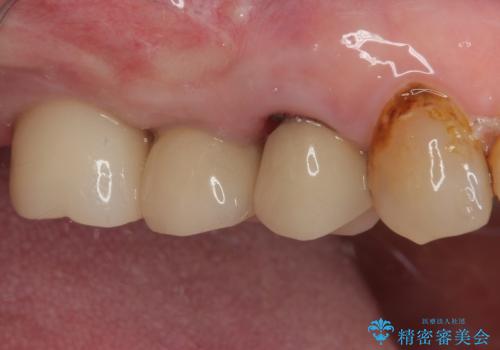

埋入時に十分な安定値が獲得でき、埋入した際に仮歯を装着することができました。

術後の経過は安定しており、抜歯から3ヶ月で治療を終えることができました。